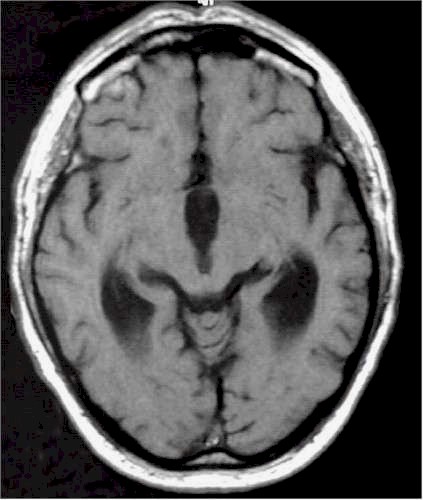

Idrocefalo

"normoteso" alla RM. |

Esito

postventricolocisternostomia. |

Le

indagini neuroradiologiche (TC e RM encefaliche) spesso non mostrano

eclatanti variazioni delle dimensioni ventricolari, pur in presenza di

una scomparsa della sintomatologia. |